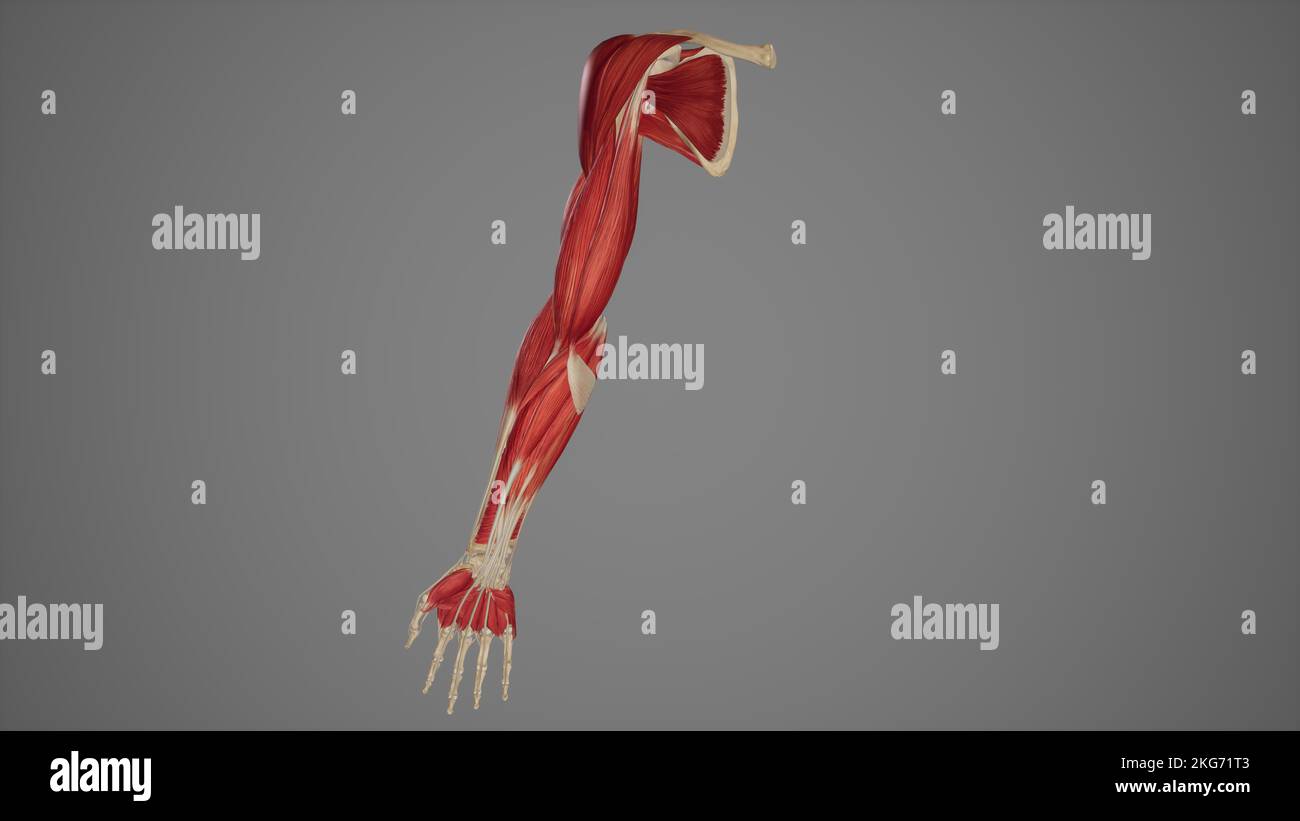

RF2JNYJM7–Präzise Knochen des Arms oder der oberen Extremität des menschlichen Skelettsystems oder Skeletts isoliert auf weißem Hintergrund 3D Rendering Illustration. Anterior und

RF2JNYJM8–Genaue vordere oder vordere Ansicht der Knochen des Arms oder der oberen Extremitäten des menschlichen Skelettsystems isoliert auf weißem Hintergrund 3D Rendering Illustration. Ein

RF2JNYJJK–Genaue 3-Viertel-Vorderansicht oder Vorderansicht der Arm- oder oberen Extremitätenknochen des menschlichen Skelettsystems isoliert auf weißem Hintergrund 3D Rendering il